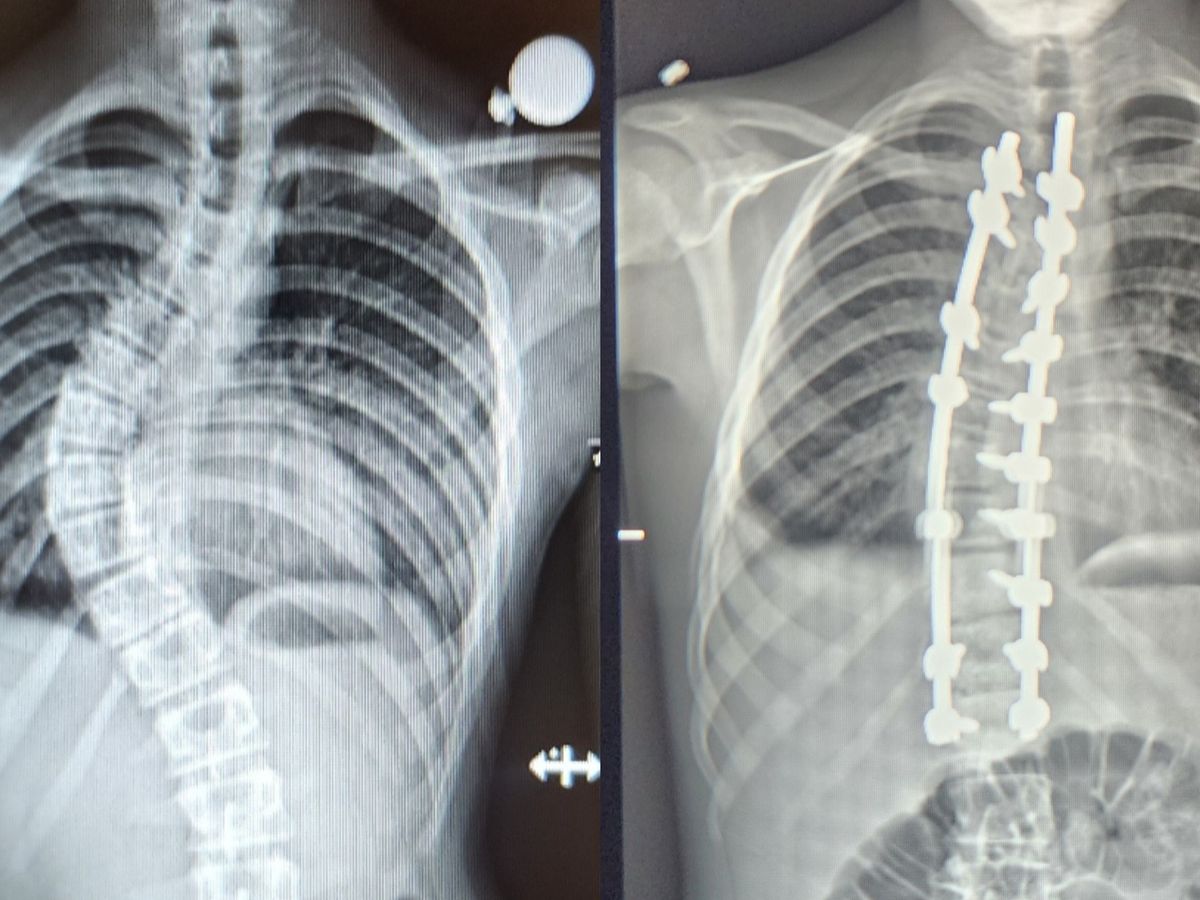

Kayden went into surgery today to have a Spinal Fusion to correct a 60 degree curve that appeared within the past year. Due to the rapid development, he was given a time-line of several months before the curve got significantly worse, and the decision was made to go forward with the surgery to avoid further damage and a difficult life leading to complications such as degenerative disc disease and and potentially being wheelchair bound.